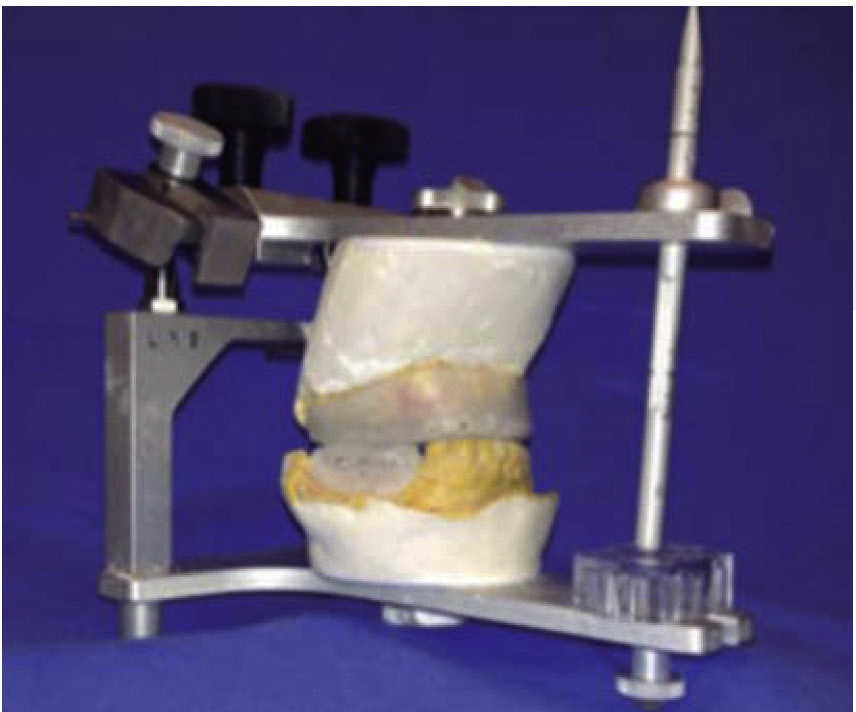

Femenino de 73 años con diagnóstico de fractura de cuerpo mandibular izquierdo por proyectil de arma de fuego (Figura 12). Paciente refiere que es asaltada en la vía pública, le retiran su vehículo y al mostrar resistencia le disparan a dos metros de distancia. Acude a nuestro hospital ocho días posteriores al evento, refiere ingresada previamente en otra casa de salud. A la exploración física presenta zona hiperémica y aumento de volumen en región submandibular izquierda fluctuante. Con orificio de entrada a nivel submandibular izquierdo con presencia de secreción blanca fétida, y orificio de salida a nivel cervical derecho cicatrizado. Intraoralmente edéntula parcial con múltiples focos sépticos en maxilar, en fondo de saco mandibular izquierdo un resto radicular de primer molar en línea de fractura. Movilidad del segmento mandibular importante por fractura de cuerpo que dificulta la deglución.

Se inicia tratamiento terapéutico de inmunización, antibioticoterapia, analgesia, extracción de focos sépticos y lavados mecánicos de la herida. La paciente no cuenta con prótesis ni parcial ni removible por lo que para establecer la relación intermaxilar y altura facial se confeccionan férulas de Gunning (Figura 13). A los diez días del tratamiento inicial se encuentra con adecuada cicatrización a nivel alveolar, con presencia de secreción no fétida a nivel de herida mandibular y se procede a realizar el segundo procedimiento mediante un abordaje extraoral con una placa de reconstrucción mandibular 2.4 y una placa 2.0 para un segmento óseo (Figuras 14 y 15). Se otorga el alta, acude a valoraciones periódicas con buena cicatrización (Figura 16), y adecuada movilidad mandibular. A las tres semanas posteriores a la reconstrucción se indica a la paciente iniciar tratamiento protésico para su rehabilitación.